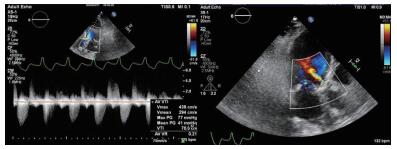

(2)血管造影明确双侧髂股动脉入路情况,选择条件更好的一侧进行手术本病例通过超声引导下穿刺左侧股动脉,但J型导丝难以通过股左侧髂总动脉,提示血管可能存在严重狭窄。随后的造影可见双侧髂总动脉均有不同程度的病变,右侧相对较好(图 2A),故选择右侧作为主入路进行手术。超声引导下穿刺右侧股动脉,置入19 F大鞘内芯,通过有阻力,考虑血管条件差,放弃置入19 F鞘。因瓣膜输送系统的外径与16 F大鞘外径相当,采用无鞘植入的方案,改成16 F cook鞘置入,顺利通过。

| A:外周血管造影;B: 20×40 mm Z-Med球囊行Balloon Sizing;C:植入26 mm Venus-A瓣膜后复查造影;D:复查外周血管入路造影 图 2 患者造影 |

明确冠状动脉情况:该患者有右冠PCI手术史,合并高血压和糖尿病,可能存在需要处理的冠脉病变,所以在置入大鞘后对该患者进行冠脉造影检查,结果提示右冠支架通畅,前降支及回旋支轻-中度狭窄,无需干预处理。

(2)选择合适大小的球囊进行Balloon Sizing测量:在明确上述情况后,还需要选择合适的球囊进行Balloon Sizing测量,同时观察冠脉血流情况进一步评估瓣膜释放后可能出现的冠脉堵塞情况。因术中基于超声测得的瓣环内径为2.11 cm,故选择20 mm×40 mm Z-Med球囊进行测量,在球囊膨胀到最大程度时,可以看到球囊两侧仍存在少量反流,且无明显腰征,左冠及右冠血流通畅(图 2B)。

选择合适大小的瓣膜植入并评估;根据超声和球囊测量的结果,针对该患者,最终选择26 mm Venus-A瓣膜进行手术,植入位置理想,几乎无瓣周漏和跨瓣压差,冠脉血流未受影响(图 2C),复查外周血管造影提示未见明显狭窄及出血(图 2D)。